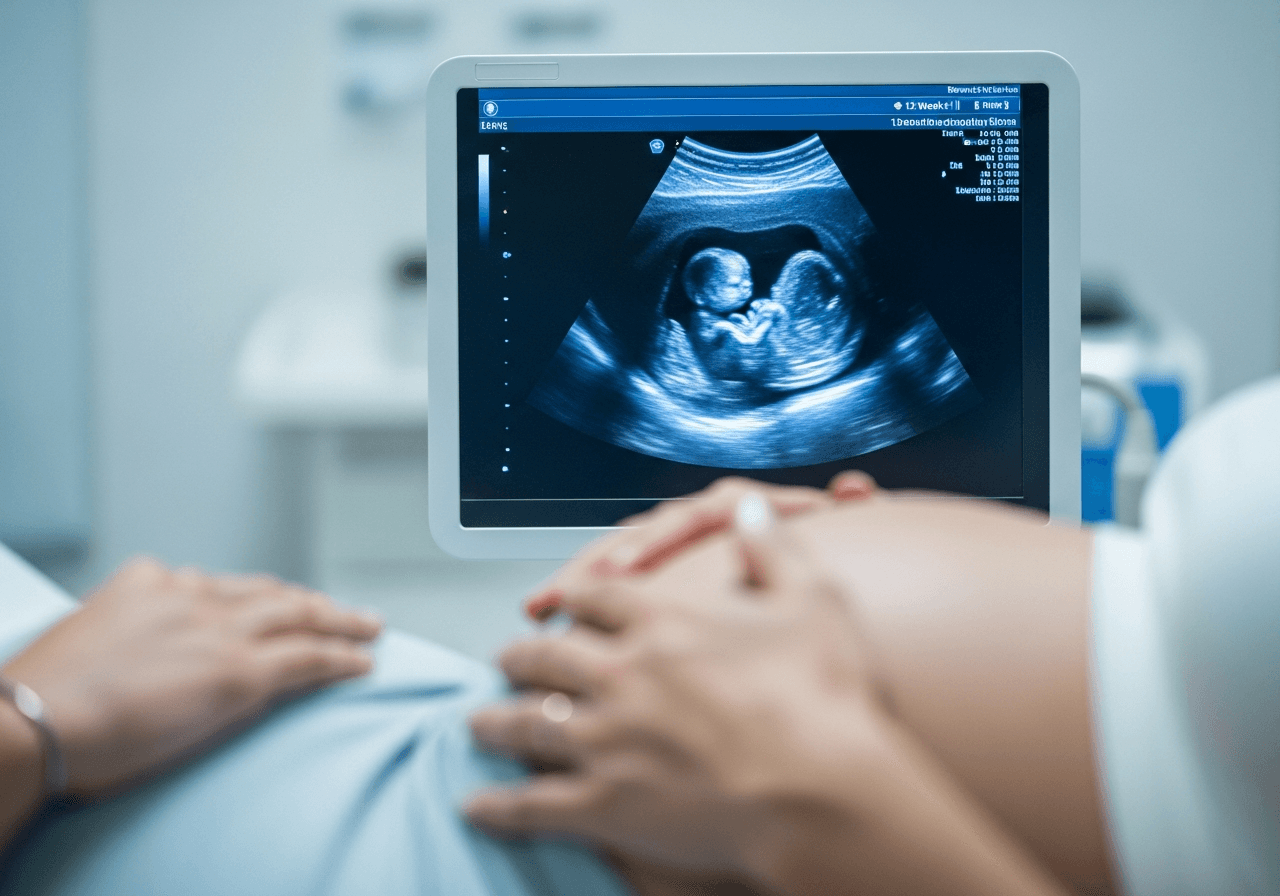

L'échographie de début de grossesse

Après un test de grossesse positif en PMA, une échographie précoce est réalisée vers 6-7 SA pour confirmer la grossesse, vérifier sa localisation intra-utérine et détecter les battements cardiaques. C'est un moment particulièrement émouvant après un parcours parfois long.

Le principe est identique, mais elle est souvent réalisée plus tôt (vers 6-7 SA) qu'en grossesse spontanée. L'équipe sera attentive à vérifier le nombre d'embryons implantés, les grossesses multiples étant plus fréquentes après PMA. C'est un moment très attendu et émouvant après le parcours de PMA.